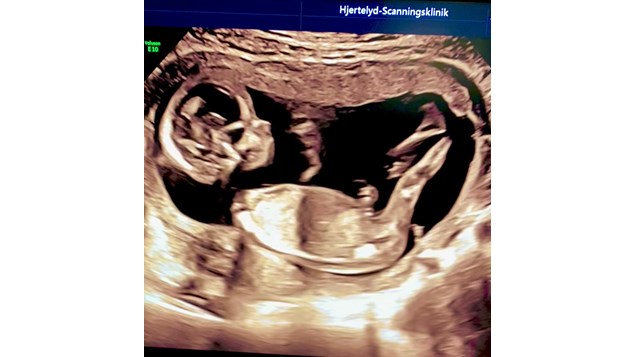

TIDLIG KØNSSCANNING

Fra graviditetsuge 14+0 kan det næsten altid lade sig gøre at identificere jeres barns køn. Om I vil vide kønnet inden fødsel - er helt op til jer. Vi kan sagtens kigge ind til den lille og jeg kan lave en grundig undersøgelse af organsystemer, vækst og trivsel - uden at I får kønnet oplyst.

Den lille er bare 14 uger. Vægten er ca 100 gram. Organerne er stort set alle udviklet nu, og baby skal 'bare' vokse sig færdig.

Kan du ud fra filmklippet se barnets køn ?

Populær tidlig kønsscanning tilbyder forældre valgmulighed om at kende barnets køn fra 14. uge af graviditeten